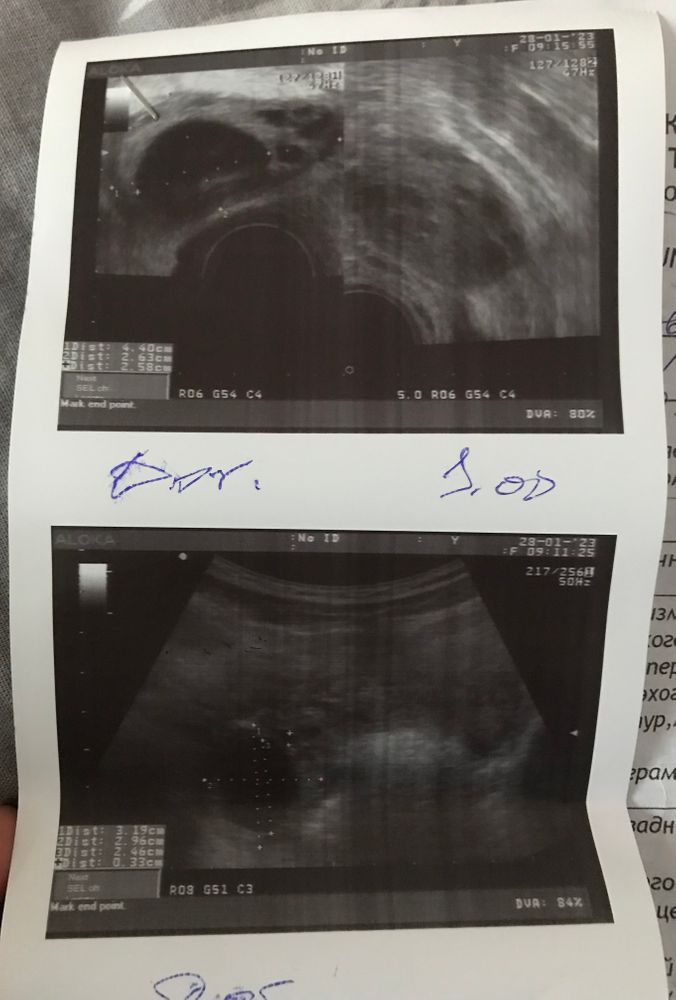

Здравствуйте девушки. После узи не могу понять какой из снимков это «трансабминальное узи»(брюшная полость)

а какое «трансвагинальное» (вагинально). Или это одно какое-то просто с разных ракурсов.